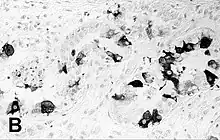

Immunohistochemical staining of the lung of a seal with PDV infection